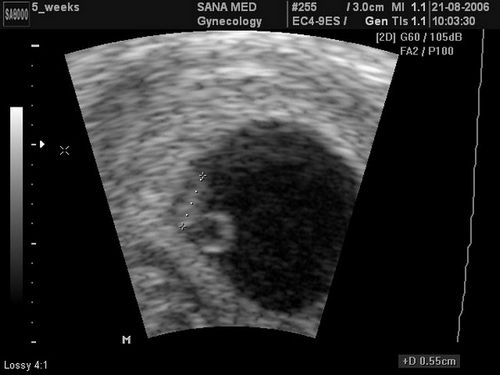

В першу чергу це стосується УЗД, оскільки розгледіти що-небудь ще не можна, тому побачити, як виглядає плід в 2 тижні навряд чи вдасться. А незначне збільшення матки може бути лише свідченням майбутнього початку місячних. До того ж, про доцільність ультразвукового дослідження на такому ранньому періоді ведуться суперечки, оскільки воно може негативно впливати на майбутнього малюка. Підтвердити або спростувати це твердження неможливо в силу неприпустимість подібних досліджень, тому лікарі намагаються утримуватися від таких призначень. До того ж в цей момент результат можуть дати набагато шкідливіші методи діагностики.